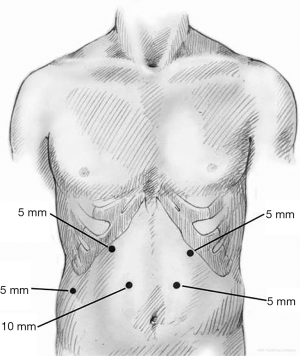

The abdomen is entered away from any previous incisions, usually in the right upper quadrant (RUQ), using a blunt port and cut down technique. Once the abdomen is insufflated to 15 mmHg, a 5 mm 30-degree camera is introduced and the abdominal cavity is inspected. The remaining ports are placed under direct visualization. Five ports are generally required to perform the procedure (Figure 2); one port at each subcostal midclavicular line, one paramedian port through each of the rectus muscles midway between xiphoid and umbilicus approximately 4 cm apart, and one subcostal right midaxillary line. All ports are 5 mm ports aside from the 10 mm right paramedian port. The patient is then placed in steep reverse Trendelenburg and a liver retractor (Lapro-Flex Triangular Retractor, Mediflex, Islandia, NY, USA) is introduced through the right midaxillary port to expose the right crus.